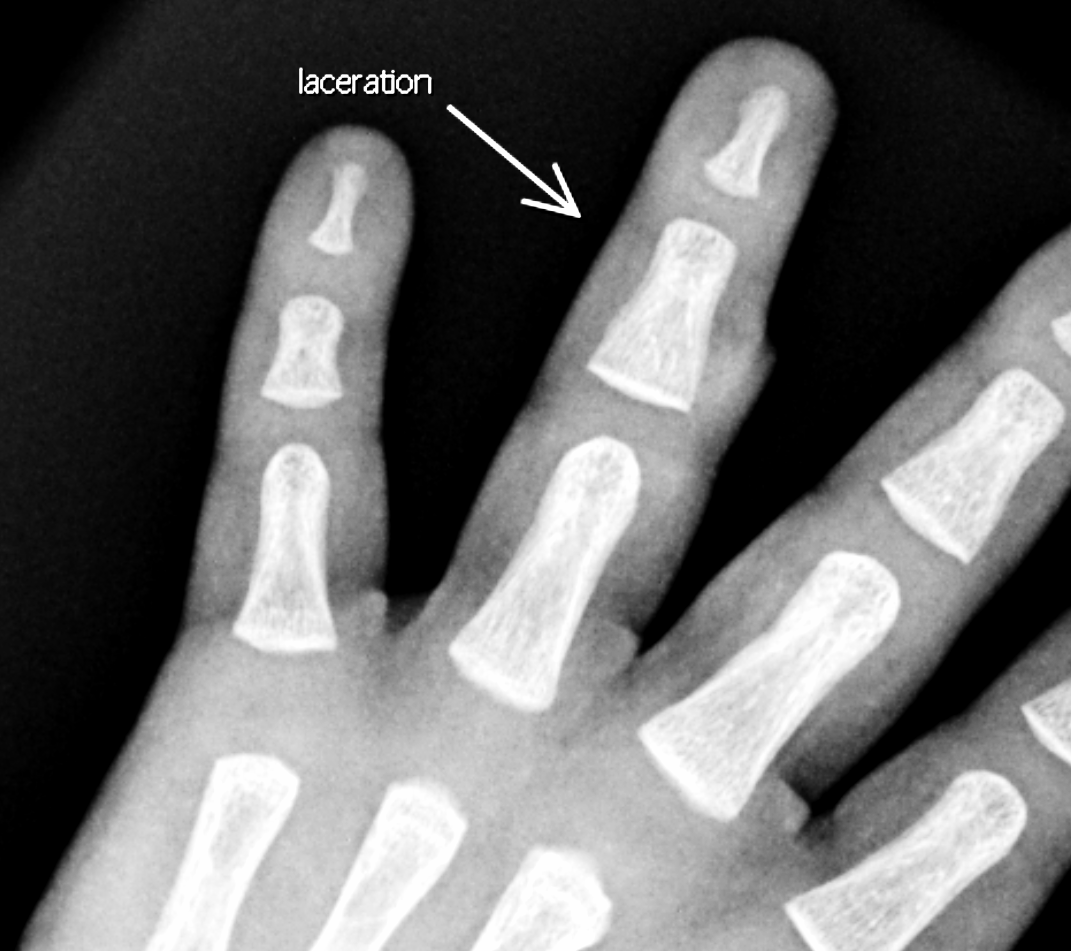

Section 1 Submit Findings CB1550 Findings Skeletal Survey - Technique Check Skull AP/Lat Yes No Cervical and Thoracolumbar spine Yes No Chest X-Ray Yes No Ribs – Left/Right Oblique Yes No Abdominal X-Ray Yes No Pelvis with both hips Yes No Bilateral Humerus, Forearm, Hand Yes No Bilateral Femur, Tibia/fibula, feet Yes No Any additional lateral views of the extremities Yes No The exam is over or under penetrated. Yes No The exam may or may not be limited by overlying structures or soft tissues, body habitus, patient positioning, support devices, or motion. Yes No The area of concern is indicated by the patient, technologist, or care provider. Yes No The area of concern is included on the exam. Yes No Soft Tissues There is soft tissue swelling, indistinctness of fat/muscle planes, gas, or laceration in the area of clinical concern. Yes No There is an effusion, fat pad displacement, or fat fluid level. Yes No There is a radiodense or lucent foreign body. Yes No There are other densities, calcifications, post-surgical changes, or support devices in the soft tissues. Yes No Any support lines/tubes. Yes No Bone There is a break or interruption of the continuity of the cortical or cancellous bone. Yes No There is overriding of the trabeculae with apparent sclerosis. Yes No There is displacement of a fracture fragment. Yes No There is bowing of the bone in addition to the fracture at the apex of the bowed bone concerning for the greenstick. Yes No There is a spiral fracture of the leg concerning for toddler’s fracture. Yes No There is abnormal angulation or bulging of the cortical surface relative to the normal cortex which could be from a buckle or torus fracture. Yes No There is a displaced fragment which may be from avulsion by a tendon, ligament, or joint capsule or from a comminuted or other fracture. Yes No The stress trabeculae or other trabeculae of the cancellous bone are interrupted or otherwise abnormal. Yes No There is subperiosteal or endosteal reaction which could indicate a healing or subacute fracture or other abnormality. Yes No There is hard/soft callus formation. Yes No There is remodeling of the bone. Yes No There is a corner fracture or metaphyseal lesion that could be from nonaccidental trauma. Yes No There are multiple fractures of different ages. Yes No There are vertebral body/spinous process fractures. Yes No There are rib fractures. Location - posterior or lateral. Yes No There is scapular/sternal fracture. Yes No There are fractures of the digits. Yes No There are wormian bones. Yes No There are intrasutural bones. Yes No There is metaphyseal abnormality (lucencies, increased density, erosion) which may be from something other than injury such as stress, metabolic disease (e.g. rickets with loss or distortion of the zone of the provisional calcification), neoplasm (e.g. leukemia), heavy metals, inflammation, or infection. Yes No There are metaphyseal spurs. Yes No There are bony deformities involving multiple bones. Yes No The bones are gracile. Yes No There are non-healing fractures. Yes No There is/are focal or multifocal lytic/lucent, blastic/sclerotic or mixed density lesion(s) or other abnormality. Yes No Overall bone density is increased or decreased with or without thinning or thickening of the cortical or cancellous bone. Yes No Growth plates, ossification centers, apophyses The growth plate(s) is/are abnormal. Yes No There is widening of the physis from a fracture with or without displacement of the epiphysis (Salter-Harris I). Yes No There is a fracture through the physis which then extends into the metaphysis with or without angulation or displacement (S-H II). Yes No There is a fracture through the physis which then extends into the epiphysis and is intra-articular, with or without angulation or displacement (S-H III). Yes No There is a fracture through the metaphysis, physis, and epiphysis which extends into the joint space with or without angulation or displacement (S-H IV). Yes No There is narrowing of the physis from a compression fracture (S-H V). Yes No The apophysis, epicondyle, secondary ossification center, or accessory ossicle is displaced or otherwise abnormal. Yes No The ossification centers are underdeveloped. Yes No Joints and alignment There is an effusion, fat pad displacement, or fat fluid level. Yes No The epiphysis or subchondral bone is fractured, interrupted, flattened, compressed, impacted, displaced, or otherwise abnormal. Yes No There is an intra-articular loose body or chondrocalcinosis. Yes No The joint is widened, narrowed, dislocated, malaligned, or incongruent. Yes No There is pseudoarthrosis. Yes No Other findings There are developmental changes or other anatomic variants or other existing conditions that may or may not be contributing to symptoms which can or should be further evaluated non-emergently or are otherwise incidental. Yes No The remainder of the exam is abnormal for age. Yes No The lungs show focal airspace opacity. Yes No There is pneumothorax. Yes No There is organomegaly. Yes No There is intra-abdominal calcification. Yes No There is displacement of the bowel loops. Yes No There is free intraperitoneal air. Yes No The bowel loops are dilated/obstructed. Yes No There is paraspinal soft tissue abnormality. Yes No